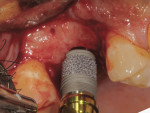

A healthy 57-year-old male patient presented interested in having his missing maxillary right first molar replaced with an implant-supported restoration in an accelerated treatment protocol. A periapical radiograph and a cone-beam computed tomography (CBCT) scan revealed that the residual height of bone from the crest to the sinus floor was 6 mm. A Trabecular Metal™ Implant (Zimmer Biomet, zimmerbiometdental.com) was chosen for this case, because it is well-suited for use in rapid recovery cases, as the implant is capable of accelerating healing and bone formation through the multiplication of naturally occurring growth factors related to bone formation, wound healing, and vascularization. A full-thickness flap was reflected using a crestal sinus approach, and the sinus lift/implant osteotomy was prepared. The implant and a BellaTek® Encode® Healing Abutment (Zimmer Biomet) were placed in a single-stage protocol. A definitive BellaTek (CAD/CAM) Abutment and an IPS e.max® crown (Ivoclar Vivadent, ivoclarvivadent.com) were placed at 5 weeks post-sinus lift and implant placement.

Timely case completion-Placing the Trabecular Metal Implant, whether in a late placement or immediate placement, offers the advantage of completing cases in a predictable, faster approach versus conventional implant therapy. A provisional restoration may be placed at the time of implant placement, followed by placement of a definitive restoration as early as 4 to 6 weeks.

Bone ingrowth and secondary stability-The bone ingrowth and secondary stability facilitated by the Trabecular Metal Implant enables completion of cases more quickly, especially in multi-unit cases.